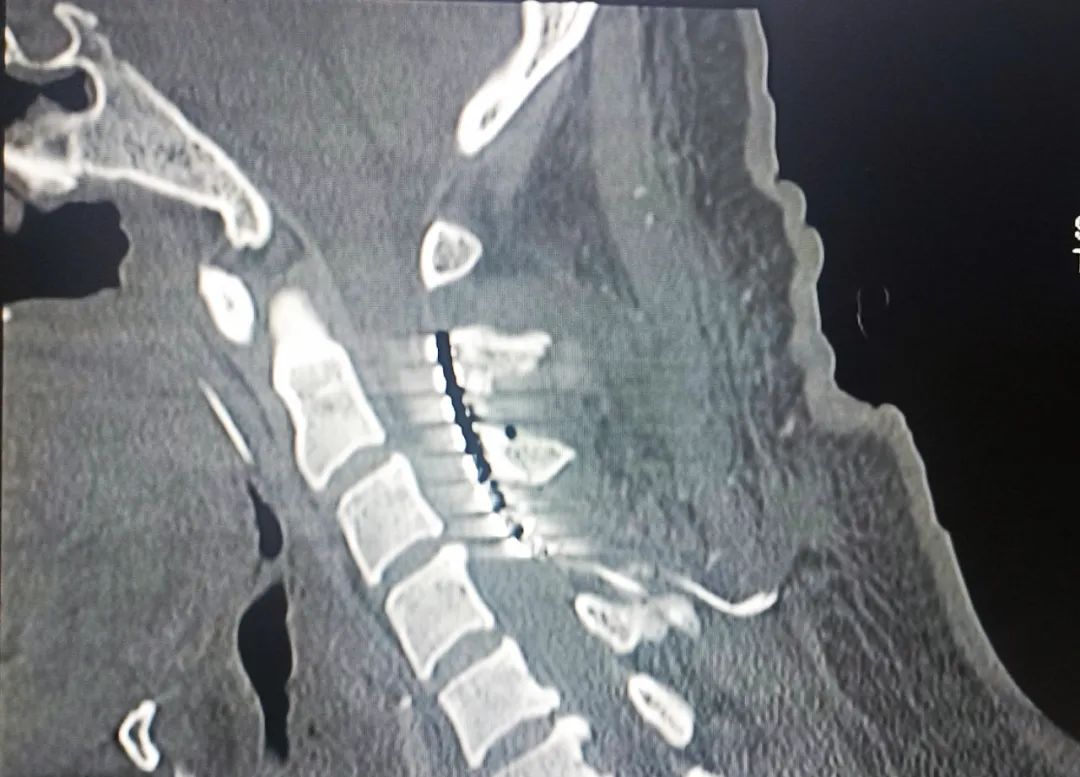

患者,男,37歲,4個(gè)月余前因“腦干出血”入住我院,經(jīng)過多次搶救治療,雖然保住了患者性命,但一直處于昏迷狀態(tài)。續(xù)繼軍主任和吳開福主治醫(yī)師,經(jīng)過全面評(píng)估及充分的溝通后,對(duì)患者實(shí)施脊髓電刺激手術(shù)促醒治療。該手術(shù)具有創(chuàng)傷相對(duì)小,安全性高,術(shù)后床旁開機(jī)程控操作簡單等優(yōu)點(diǎn)。現(xiàn)術(shù)后開機(jī)程控一個(gè)月,患者的意識(shí)障礙及肢體活動(dòng)等情況得到不同程度改善。